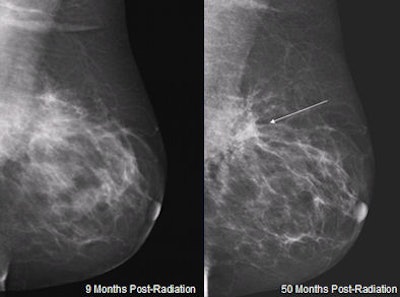

| Mammogram of 53-year-old woman nine months following MammoSite brachtherapy shows mild distortion (left image). Retraction, increased density, and moderate distortion as highlighted by arrow have developed 50 months following treatment. Courtesy of Brigham and Women's Hospital. |

Twelve patients developed moderate distortion 19 to 21 months after treatment in nearly identical patterns, plateauing at 21 months. For two patients, symptoms of distortion began to minimize starting three years after treatment.

One patient developed severe distortion at 23 months. A total of five patients had additional imaging procedures, including ultrasound and/or MRI exams. However, none of the patients required aspiration, biopsy, or excision, Ahmed reported.